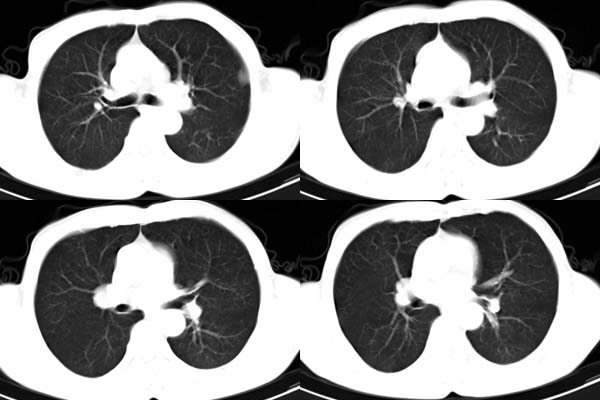

患者,男,65岁,咳嗽,胸痛

ct所见;左下肺可见片状阴影,密度不均,边缘尚清晰,胸膜方向见有条索相连,纵隔窗未见具体结节。左侧胸膜下见多个软组织结节且以宽基底与胸膜相连,右侧胸锁关节层面亦见软组织结节广基与胸膜相连。纵隔未见肿大淋巴结,气管,支气管开口正常。

左肺下叶基底段见结节样稍高密度影,内密度不均匀,边缘不清,可见索条影与邻近胸膜粘连,左侧胸膜上见多个结节影,以宽基底与胸膜粘连.纵隔不宽,内未见明确肿大的淋巴结.

考虑:周围型肺ca伴左侧胸膜转移可能性大 ,不完全除外左肺下叶炎性假瘤,左侧胸膜间皮瘤可能,建议强化ct扫描。

ct所见:左肺上、下叶近胸膜肺外带可见多个大小不等的结节灶,边界清楚,边缘比较光整。近胸膜病灶似与胸膜以宽基底紧连。提供的病史比较简单,我考虑:1、胸膜原发肿瘤可能性大(就形态来看恶性可能性不大);那么大胆的设想一下,左下叶结节是否与它有必然的联系呢?也可以是结核或周围型肺癌。2、还可以考虑为胸膜和肺内的都是转移灶,病人65岁,是不是其他部位的恶性肿瘤转移过来的呢?因为病灶比较表浅,但一侧发病较少见。3、周围型肺癌并胸膜转移的可能性比较小,一是肺内病灶较小,单发,胸膜结节相对较多,位置较远,临近胸膜无受侵。